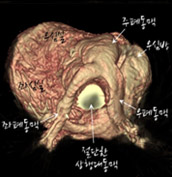

[그림3] 완전대혈관전위증 심장의 외부모습 / 내부모습

우심실과 대동맥이 연결되어 있고 폐동맥은 좌심실과 연결되어 있음